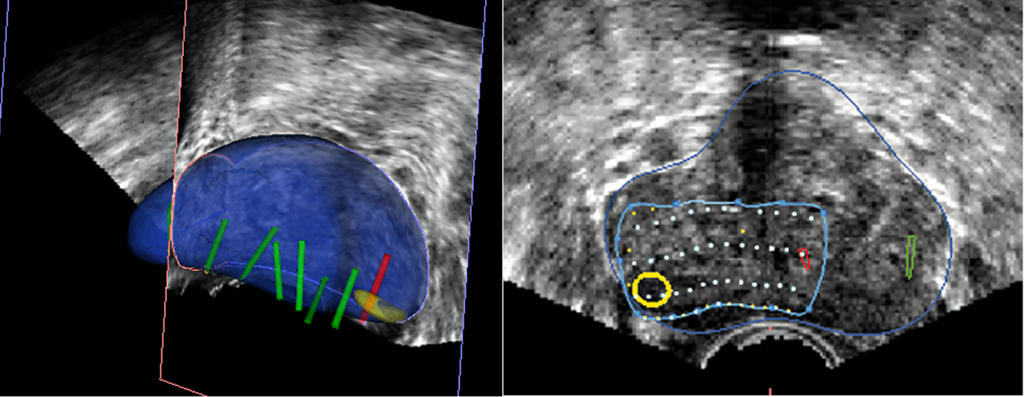

La próstata se escanea con la sonda de US. El operador define los contornos de la próstata y delinea las lesiones sospechosas a tratar en las imágenes de Resonancia. Los límites de la próstata se definen en la imagen en tiempo real de la próstata obtenida con la sonda trans-rectal del dispositivo. El software ejecuta automáticamente una “fusión elástica” de los dos volúmenes definidos, lo que conduce a una combinación tridimensional (3D) perfecta del volumen de RM con el volumen de la próstata en US. La misma fusión 3D se aplica al área sospechosa previamente identificada en la resonancia magnética y/o Biopsia por fusión que, por lo tanto, se puede identificar correctamente en la imagen en vivo de US. (Figura 3-4).